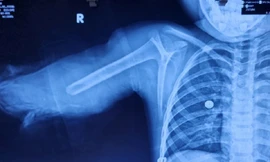

TPO - Bệnh nhi nhập viện trong tình trạng, cánh tay bên phải bị dập nát đứt lìa hoàn toàn. Điều tra bệnh sử bác sĩ ghi nhận, trước khi tai nạn xảy ra, bệnh nhi khoác một bên tay áo, bên còn lại để thõng xuống, khi ngồi sau xe gắn máy đã bị cuốn vào bánh, kéo lìa cánh tay.